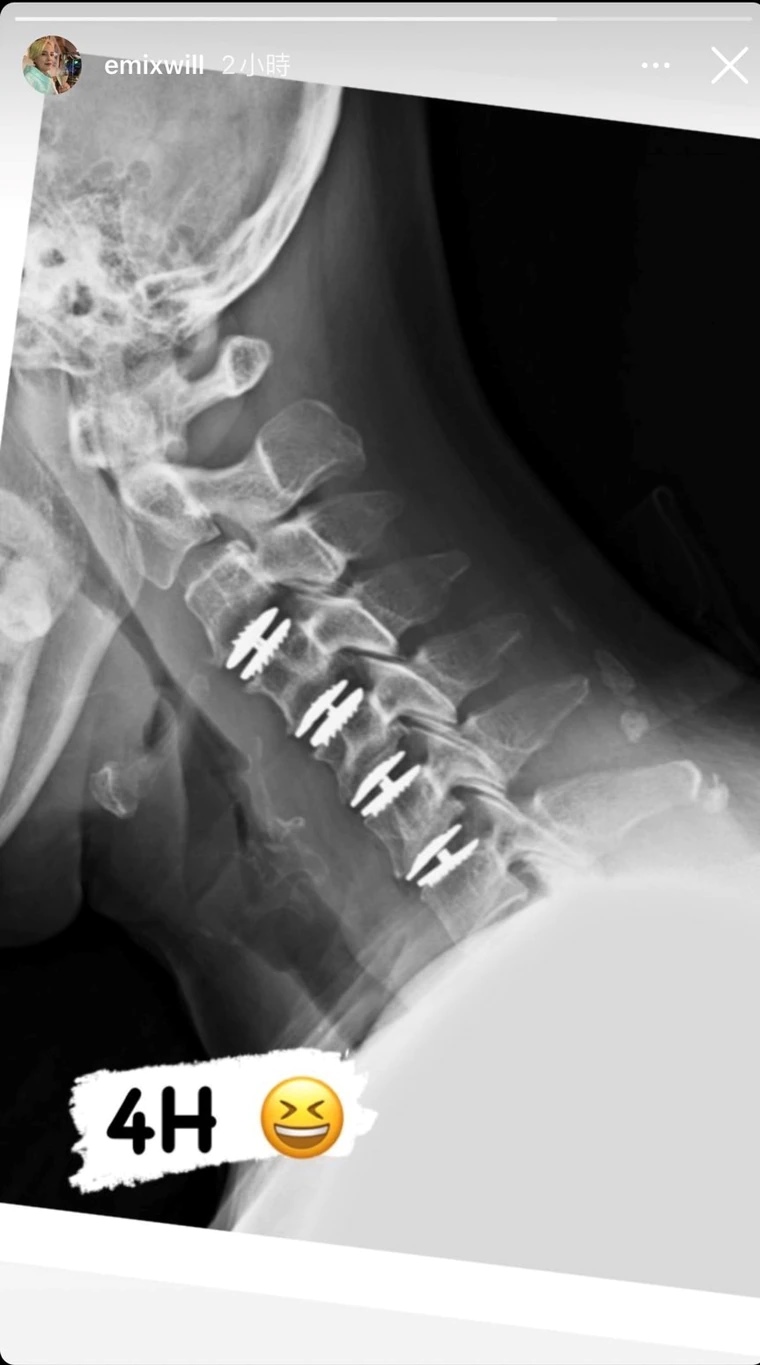

李明依5日动刀,并于9日透过脸书发文报平安,公开颈部X光片,可以清楚看到4个“H”字的人工椎间盘已经装好。但没想到在手术前一天李明依才知道,若再晚一个月健保给付1个椎间盘医材,至少可省23万台币(约3万4400令吉),质疑为什么等她的新闻出来之后政府才说要通过,更扯的是连医院的医生都不知道有这项政策。